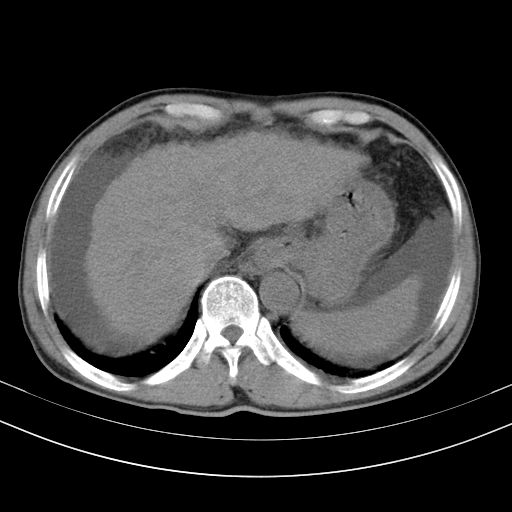

以下是引用随光逐影在2010-2-28 10:23:00的发言:[br]1)考虑肝癌;建议行ct增强扫描检查。2)肝硬化,脾大,腹水。3)慢性胆囊炎。